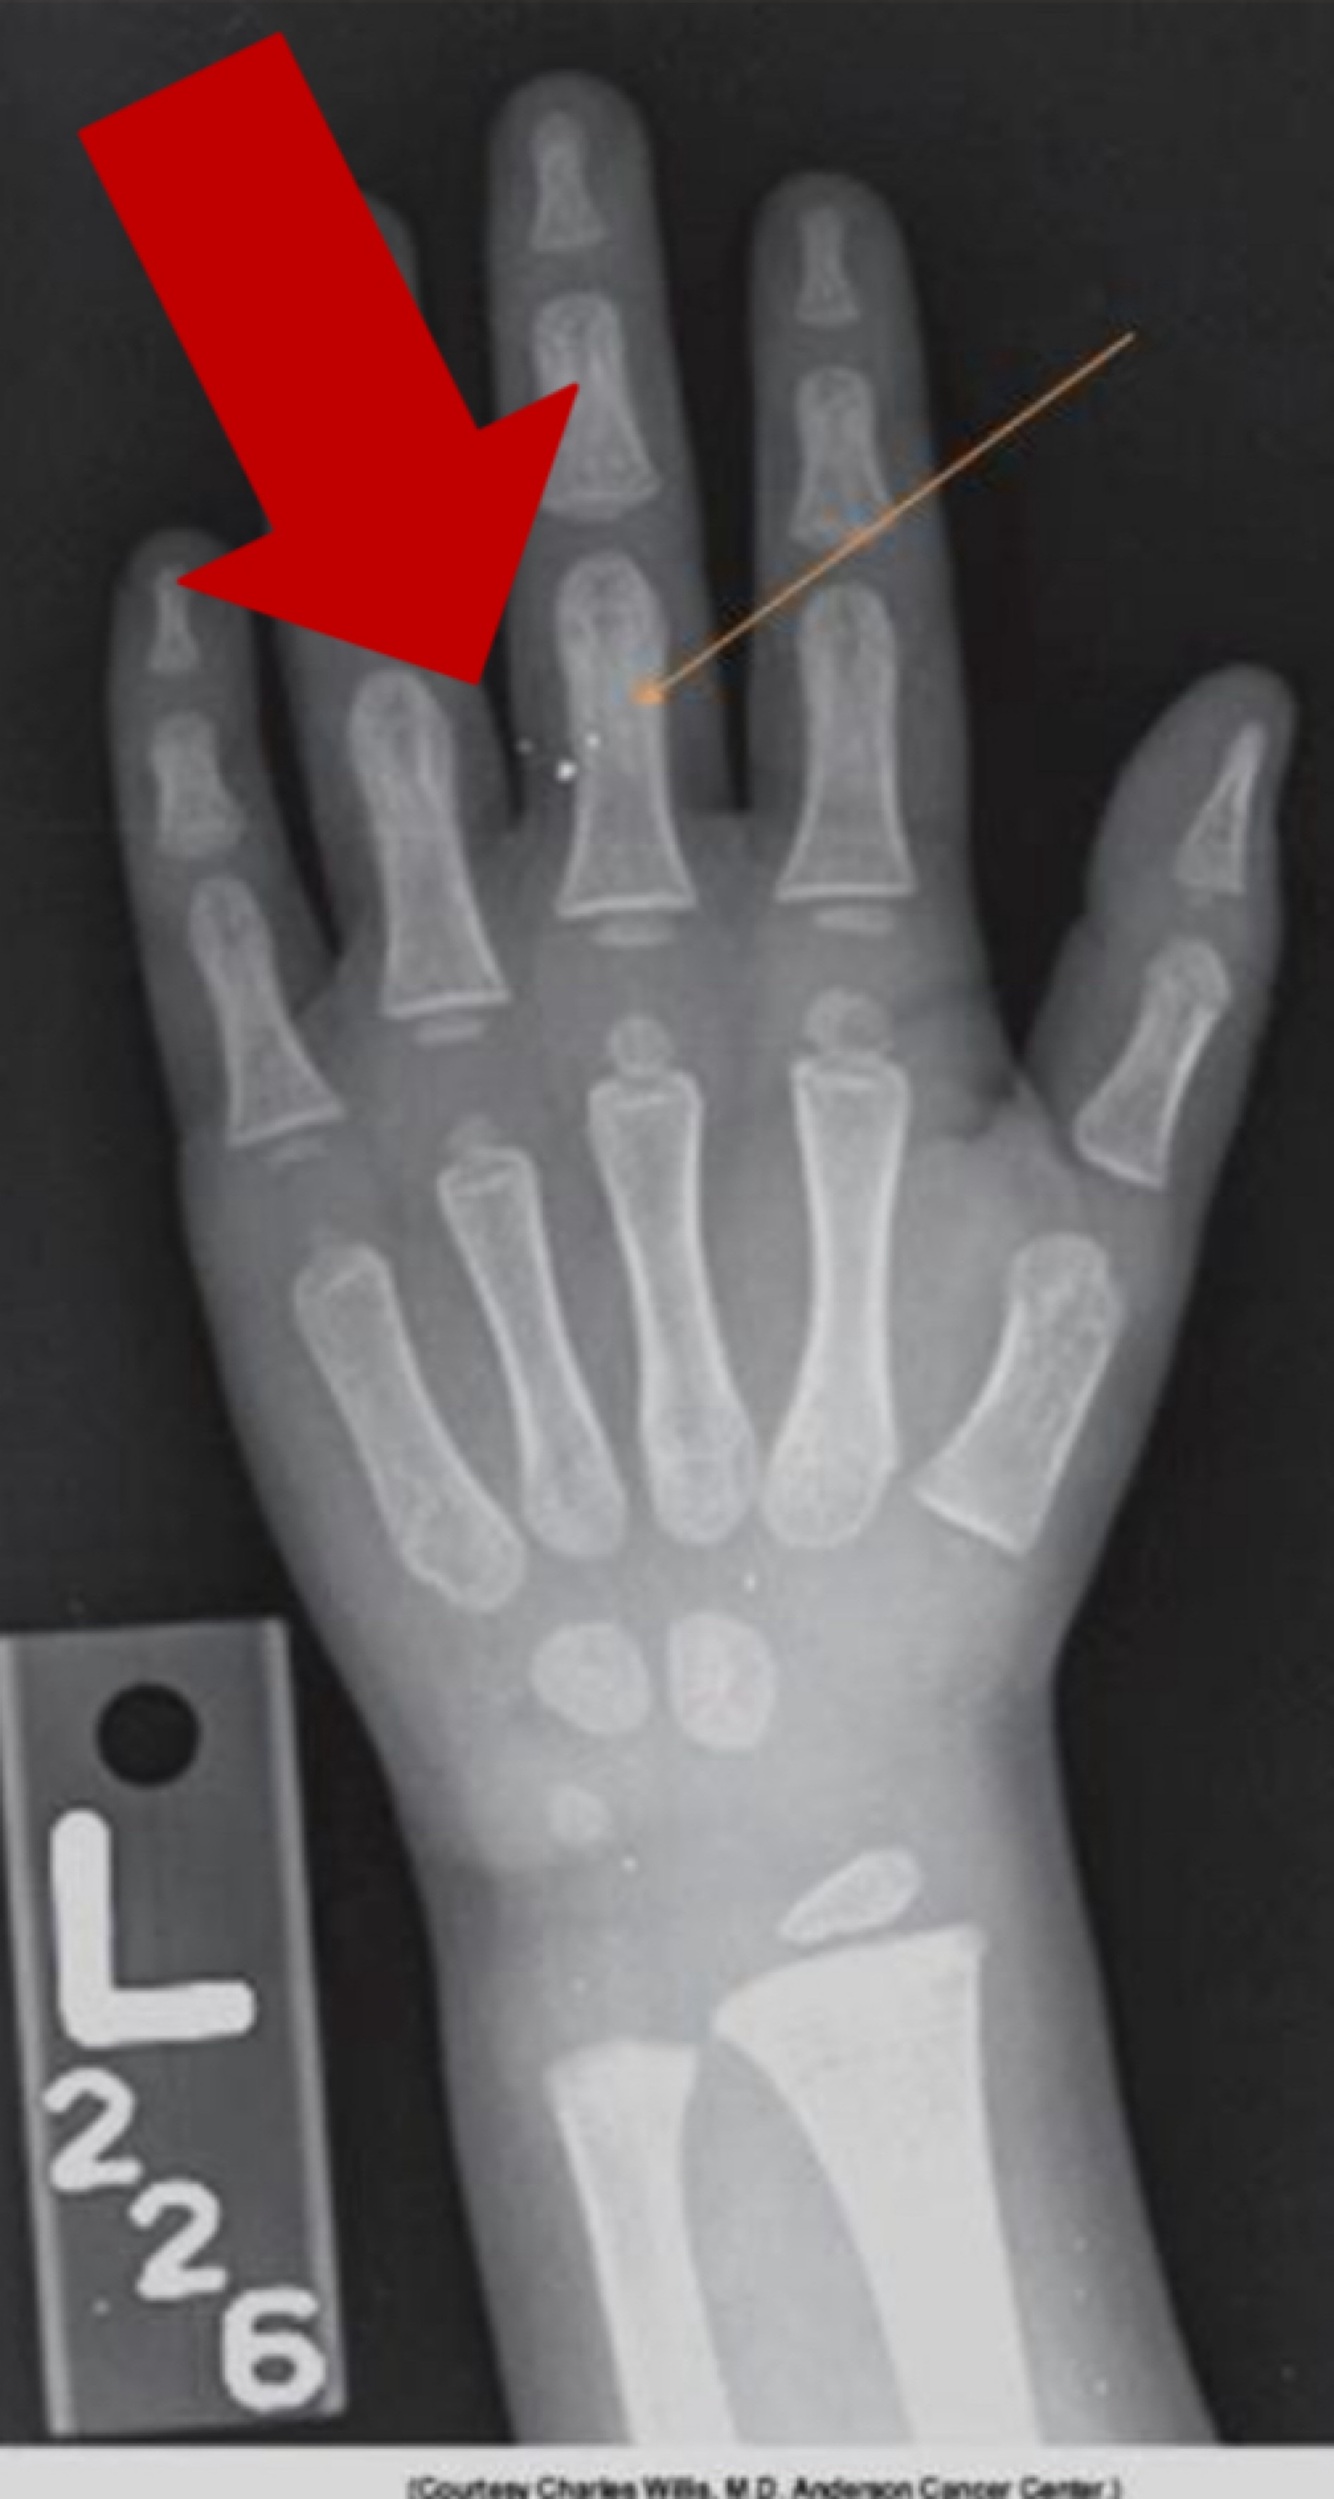

Foreign body: Acupuncture Needles